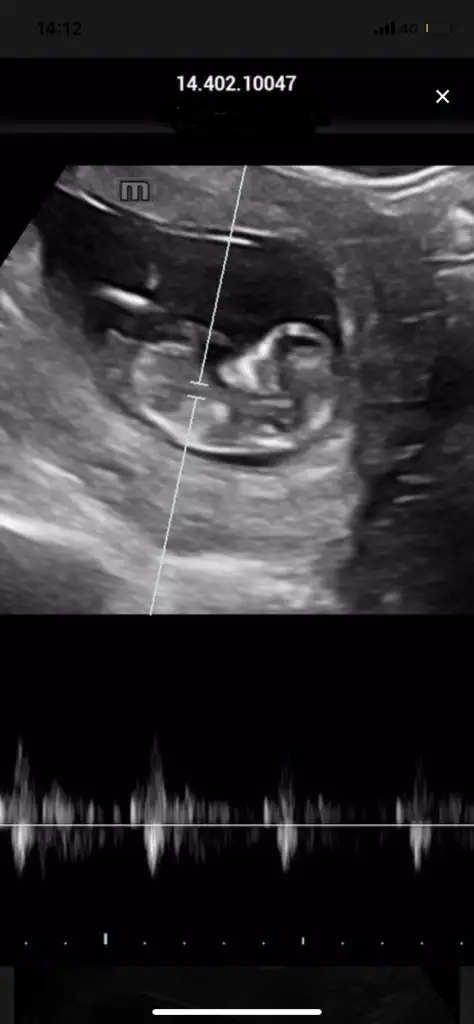

Merhaba kizlar. Son adet tarihim 23 nisan fakat geriden geliyoruz doktor gec dollenme olabilir demişti. Gecen hafta adete gore 6+4 olmam gerekirken ultrasona gore 5+5 cikti 19 haziranda cagirdi kalp atisini duyariz diye. Ama ben bu hafta yasadugim ilcedeki hastaneye gittim pazartesi gittigimde ustten hala sadece kese gorunuyordu alttan bakinca da minik bir sey gordum dedi. Bugun tekrar gittigimde ustten yine bir sey gorunmedi alttan o minik gorunen sey icin beslendigi kese dedi ve suan ultrasona gore 6+6 olmam gerekirken 5.5-6 haftalik kese 14 mm dedi. Kafam cok karisti adete gore 7+5 olmam gerekiyor ama ortadaki senaryo bu. Aranizda yasayan ya da bilgisi olan var mi? Bir terslikk olabilir mi?